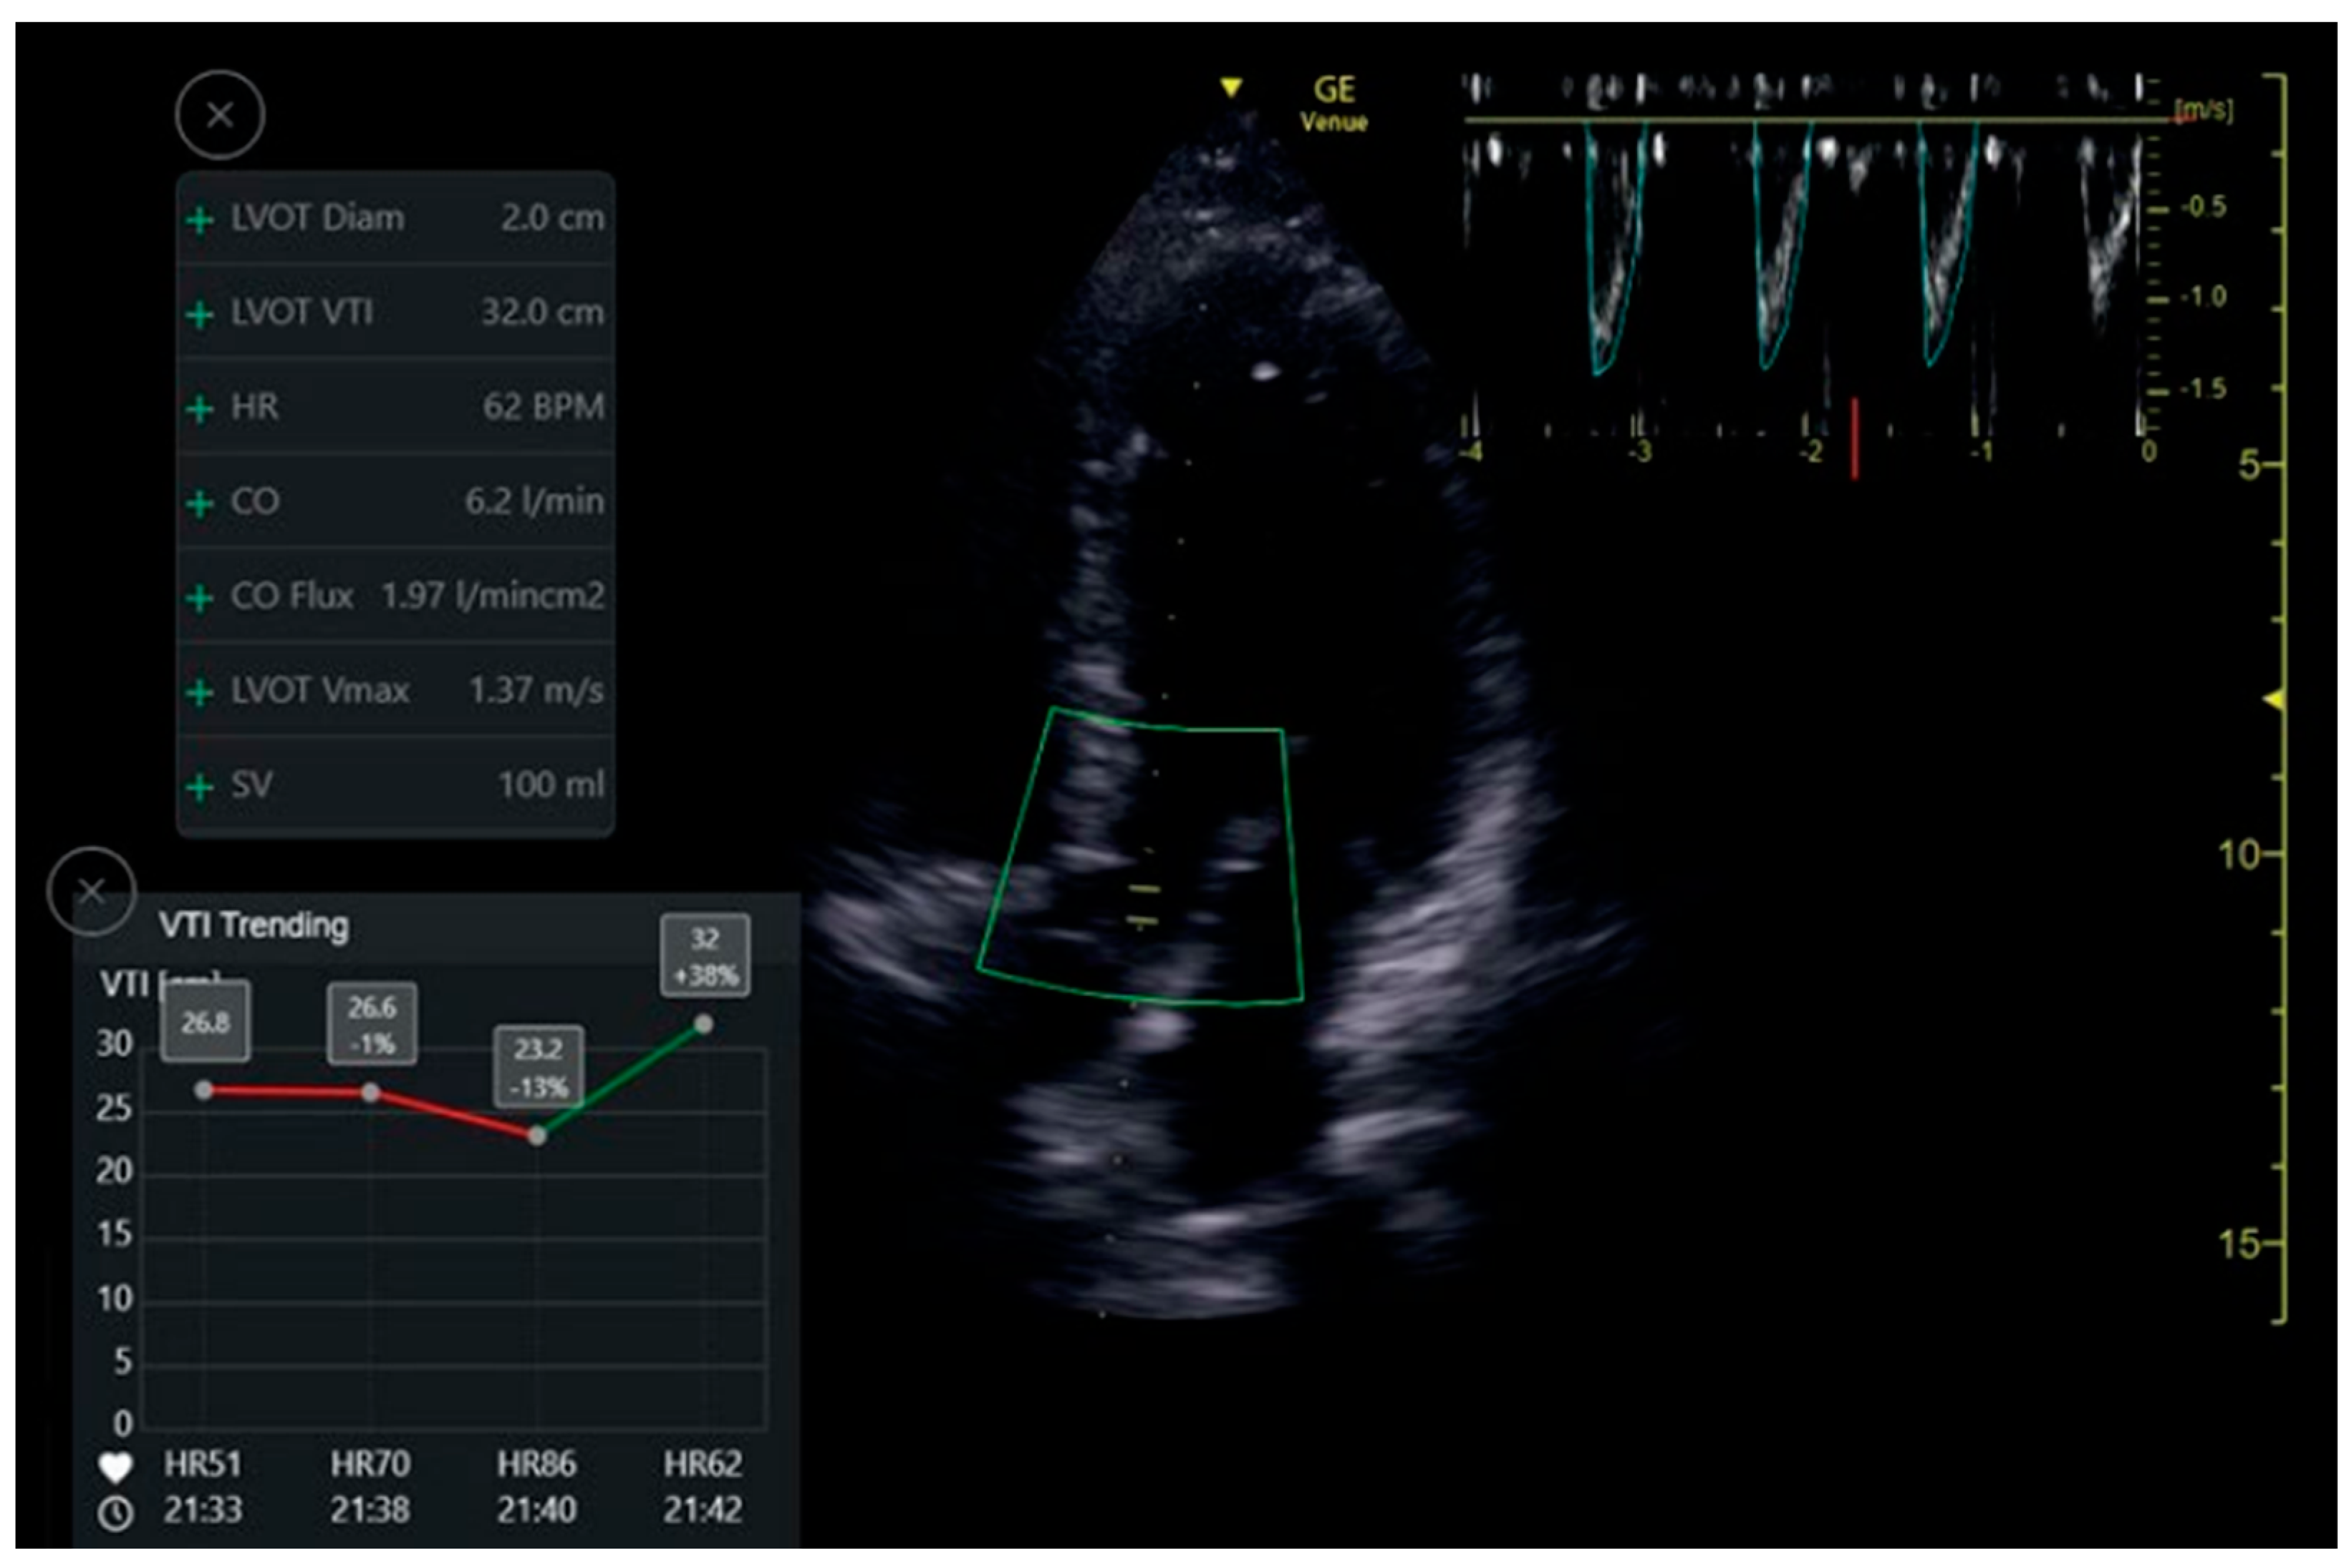

VTI Automatic Measuring Tool

The auto VTI tool is based on proprietary artificial intelligence. The tool automatically places the cursor on the left ventricular outflow tract (LVOT) and auto-traces the velocity waveforms to calculate the VTI. The tool then calculates VTI and CO by averaging all Doppler waveforms during a period of four seconds. Calculations were performed in real-time, and the results are displayed in the Results Box (Figure 5). The Quality Indicator is represented by the color of the curser placed by the system over the LVOT. It varies between green/yellow/red to represent excellent/average/unacceptable image quality, respectively.

Figure 5.

Auto VTI tool. When in Apical5Chamber-View. Auto marker placement, velocity pattern measurements and data display.

7.3. LVOT VTI

One hundred and fourteen apical five-chamber view clips were acquired from 32 patients. The clips were taken in pairs—a POCUS expert acquired a clip, and then without changing the probe position acquired a second, similar clip. Thus, two groups of paired clips were formed. Patients were primarily males (69%), with a mean age of 57.4 ± 18.5 and a mean body mass index (BMI) of 27.1 ± 5.5 (Table 1). When assessed by the Expert, the mean LVOT VTI value was 19.5 ± 4.5 and 17.7 ± 4.3 by the automatic analysis read. The Intraclass Correlation Coefficient for agreement between the automatic and physician-assessed quantifications was 0.825 (95% CI 0.659, 0.905; p < 0.001). In the high clips’ quality subgroup, the Intraclass Correlation was reduced to 0.655 (95% CI 0.013, 0.877; p = 0.024). In the medium clip quality group, the Intraclass Correlation was 0.914 (95% CI −0.077, 0988; p < 0.001) (Table 4). For the image quality agreement, we found a significant difference (p = 0.167, Fishers Exact test value—3.26, α) in the agreement of quality between the physicians’ group and the automatic tools group.

The VTI agreement proved to be very high in all levels of the acquired image quality; high, medium, and total. This finding confirms that when a quick measurement for stroke volume is needed, there is a reliable automatic tool for any level of imaging quality.